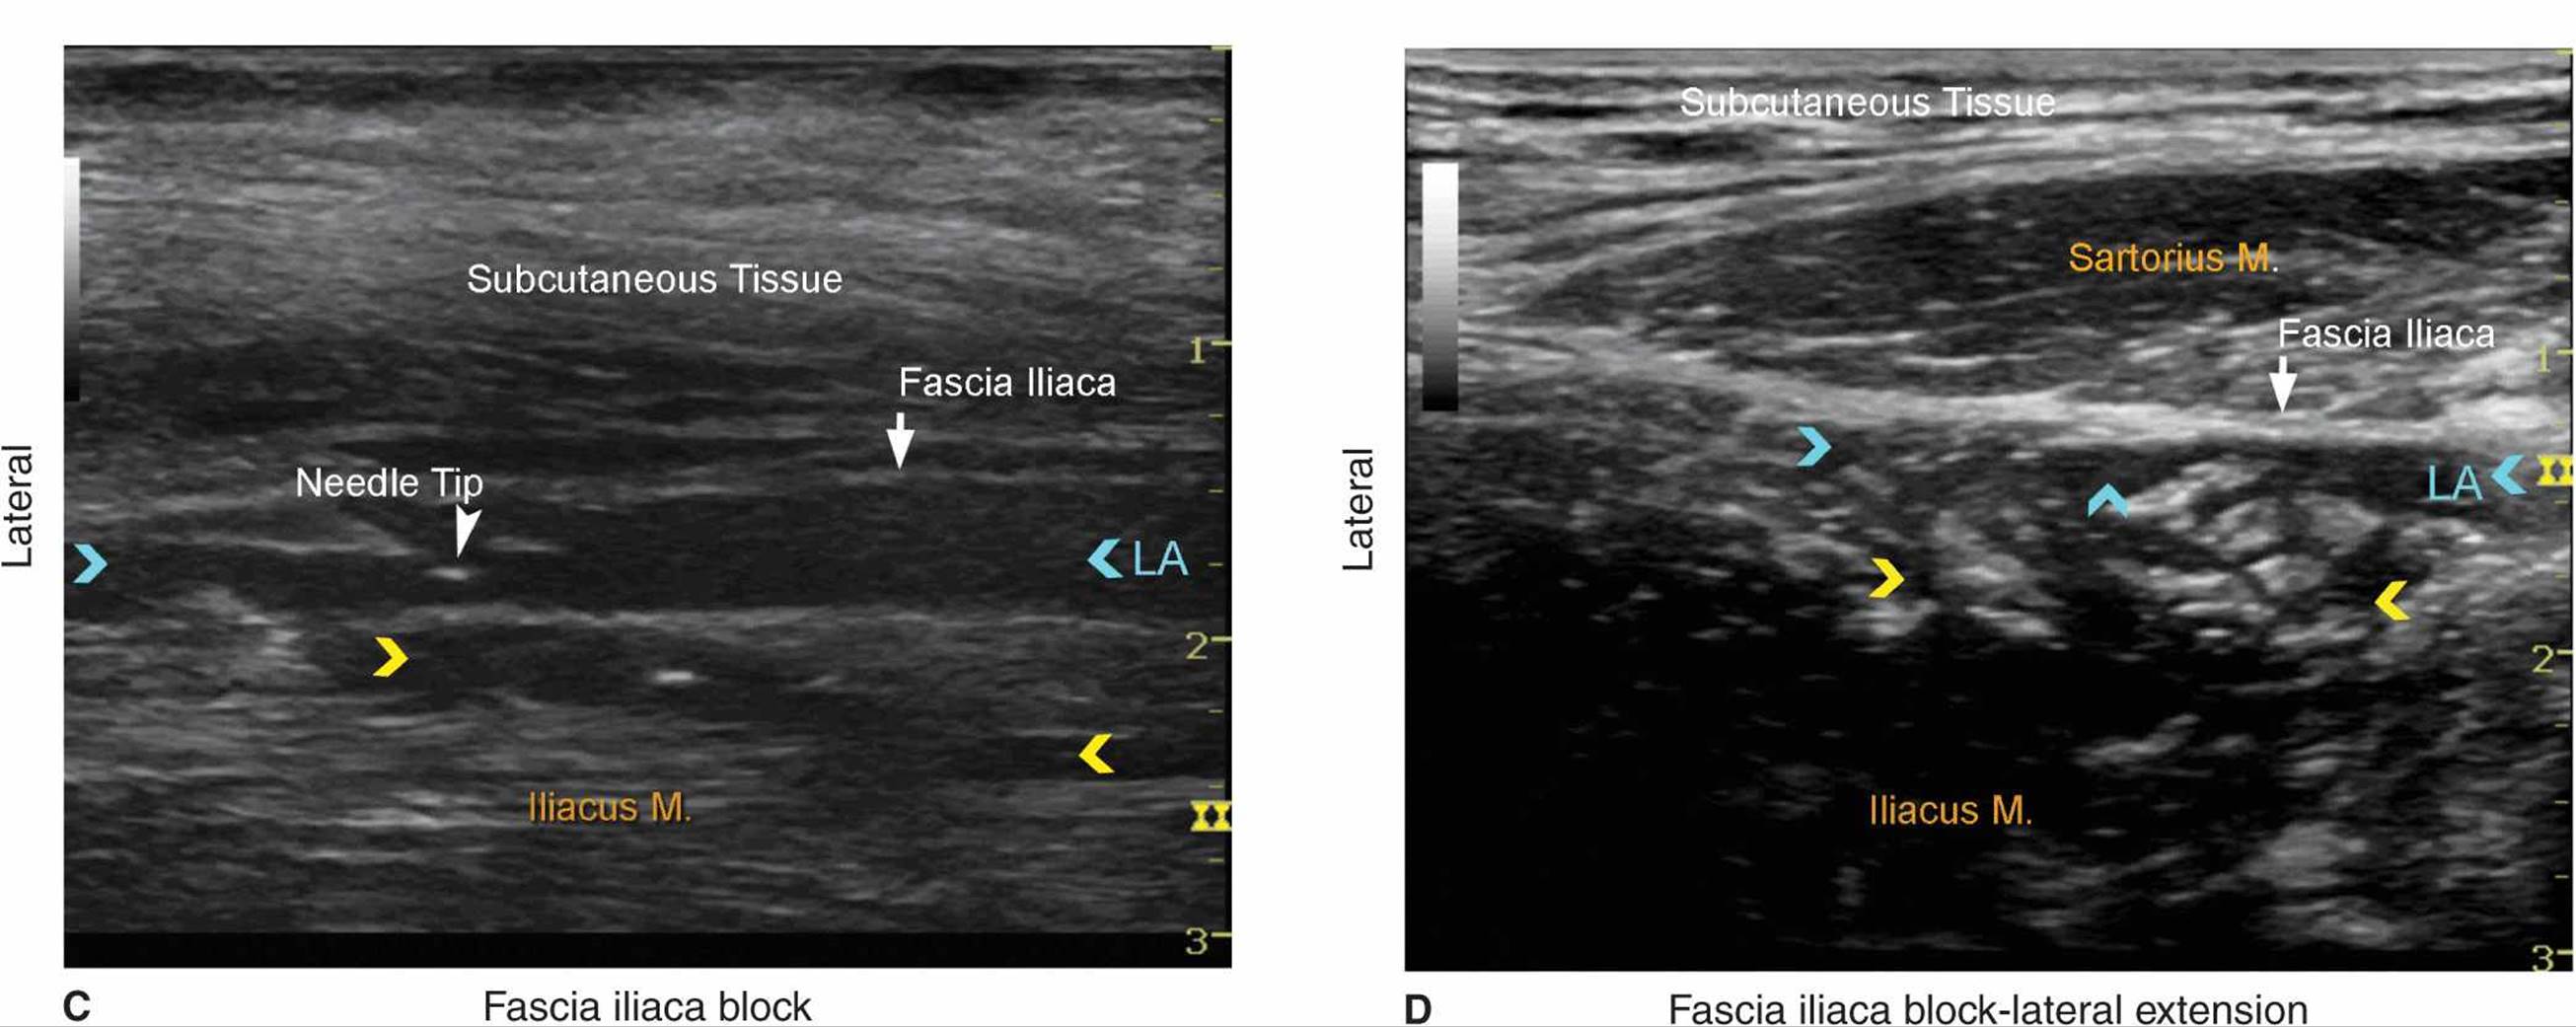

With the patient in the proper position, the skin is disinfected and the transducer positioned to identify the femoral artery and the iliopsoas muscle and fascia iliaca. The transducer is moved laterally until the sartorius muscle is identified. After a skin wheal is made, the needle is inserted in-plane (Figure 36-1). As the needle passes through fascia iliaca the fascia is first seen indented by the needle. As the needle eventually pierces through the fascia, pop may be felt and the fascia may be seen to “snap” back on the ultrasound image. After negative aspiration, 1 to 2 mL of local anesthetic is injected to confirm the proper injection plane between the fascia (Figure 36-4) and the iliopsoas muscle (Figure 36-5A, B, and C). If local anesthetic spread occurs above the fascia or within the substance of the muscle itself, additional needle repositions and injections may be necessary. A proper injection will result in the separation of the fascia iliaca by the local anesthetic in the medial-lateral direction from the point of injection as described. If the spread is deemed inadequate, additional injections laterally or medially to the original needle insertion or injection can be made to facilitate the medial-lateral spread.

FIGURE 36-5. (A) Path of the needle for the fascia iliaca block. The needle

is shown underneath the fascia iliaca lateral to the femoral artery (not seen) but not too deep to be lodged into the iliac muscle. (B) A simulated spread (area shaded in blue) of the local anesthetic to accomplish a fascia iliaca block. (C) Spread of the local anesthetic (LA) under the fascia iliaca. Some local anesthetic is also seen deep within the iliacus muscle (yellow arrows). When this occurs, the needle should be pulled back more superficially. (D) Extension of the LA laterally underneath the sartorius muscle. Some LA fills the adipose tissue between fascia iliaca and iliacus muscle (yellow arrows).